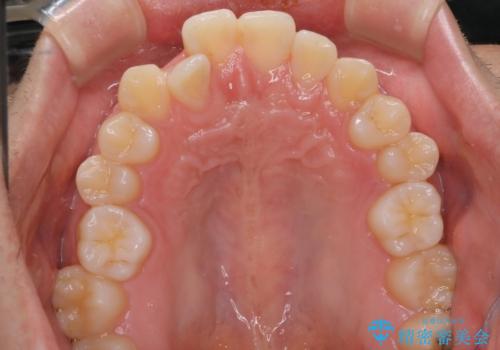

- 前歯のがたつきを主訴に来院されました。初診時、右上2番の口蓋側転位と右下7番の舌側傾斜が認められました。

インビザラインにてIPRと歯列弓拡大を行い、ゴム掛けで噛み合わせを改善する治療計画を立てました。

マウスピースの使用時間が短いため、シュミレーション通り進むか不安でしたが

治療期間1年で、主訴である前歯のがたつきを改善出来、

奥歯の噛み合わせも良くなりました。